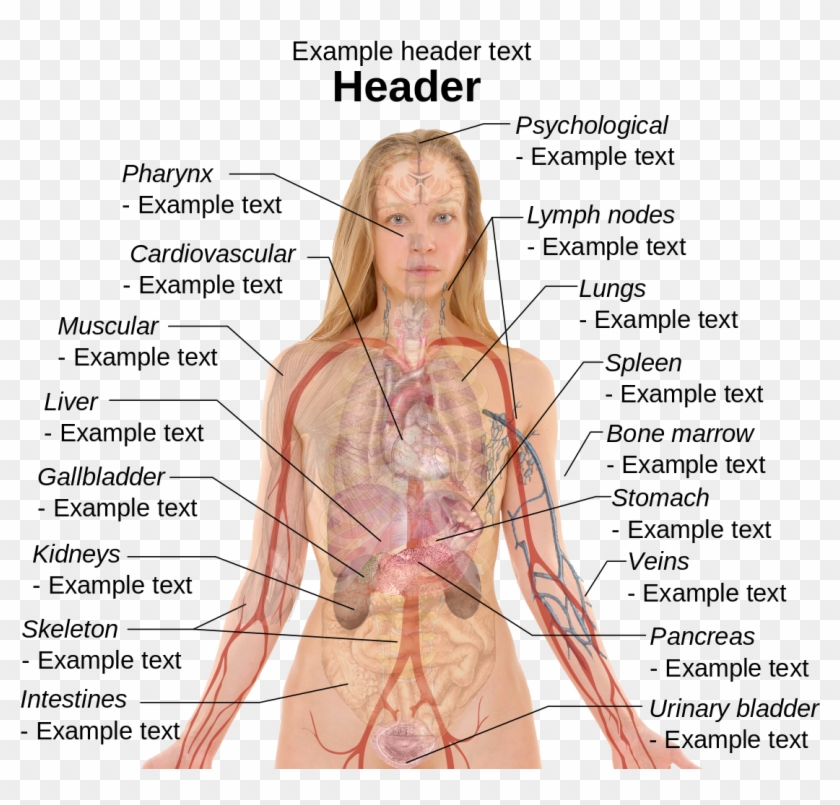

Anatomy Of Internal Organs Female – Organ Anatomy Female Anatomy …

Female Body Organs Diagram Anatomy | MedicineBTG.com

Female Human Organs Diagram | MedicineBTG.com

Human Female Organ Diagram . Human Female Organ Diagram Colorful Human …